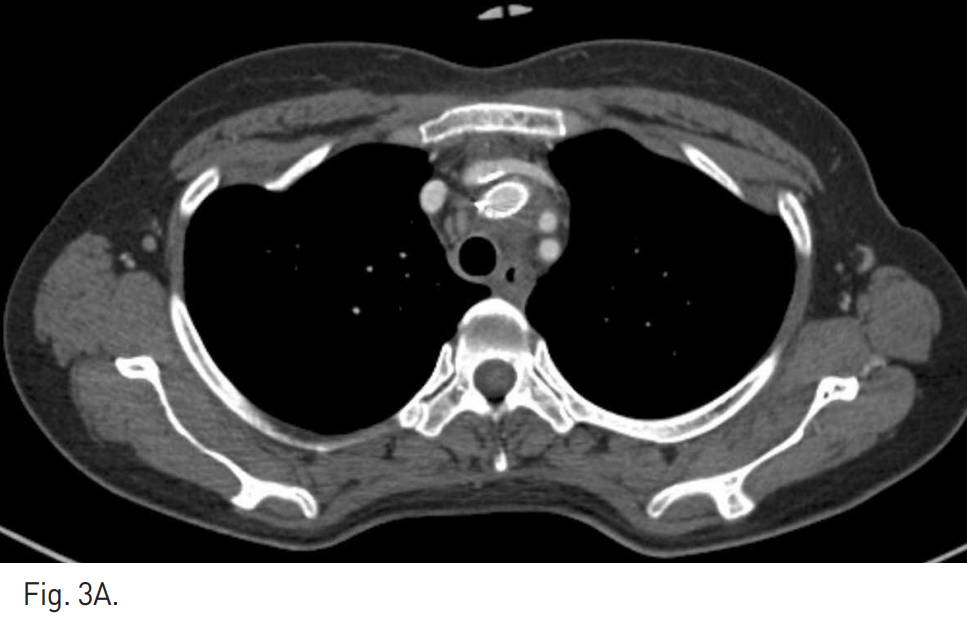

Fig. 1

A, B. Arterial phase axial (A) and coronal MIP (B) images of chest CT scan show the dissection with pseudoaneurysm formation at the right brachiocephalic trunk. Small amount of mediastinal hematoma is noted.